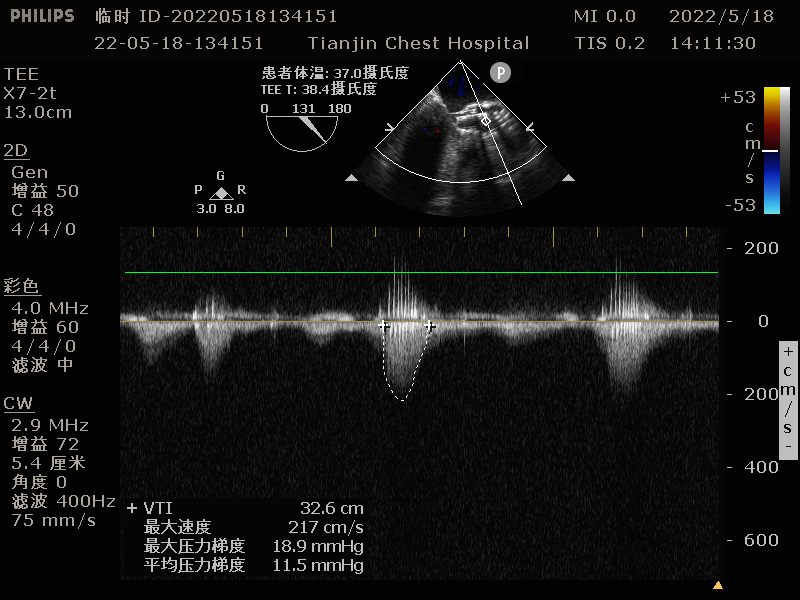

术前超声心动图:

LVEF:61%;PPG:30mmHg;LA:42mm;RA:30mm;LV:52mm;

RV:30mm;Amax:6.3m/s;mPG:95mmHg;AVA:0.6cm²。

主动脉瓣重度狭窄;

主动脉轻度反流;

二尖瓣及三尖瓣轻度反流。

术前TEE检查:TEE多普勒检查